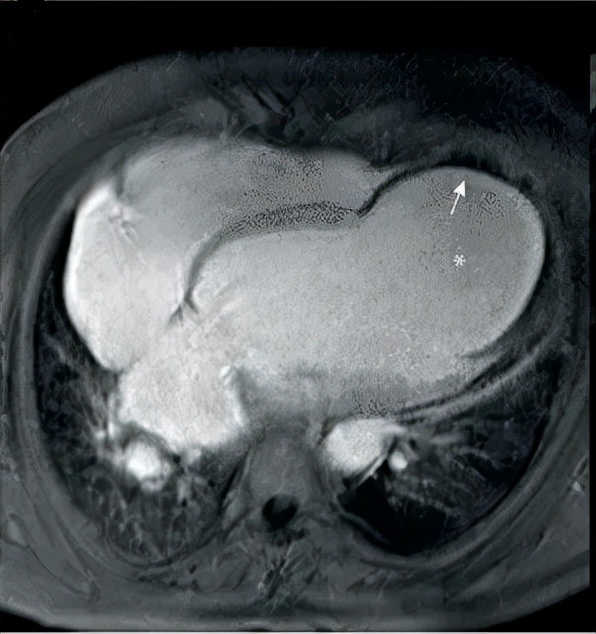

冠心病患者大面積心肌梗死後,梗死區域出現室壁擴張、變薄、心肌全層壞死,壞死的心肌逐漸被纖維瘢痕組織所替代,失去正常收縮能力,在心臟收縮和心腔的壓力作用下,病變區薄層的心室壁向外膨出,呈現反常運動。在臨床上該部位類似於向外膨出的瘤體,稱之為室壁瘤。

急性心肌梗死時,梗死心肌組織壞死、室壁變薄、收縮力喪失,心肌在癒合過程中被結締組織替代,形成薄弱的瘢痕區,心臟收縮時此區呈反向運動,膨出呈袋狀、囊狀或不規則狀,腔內無肌小梁,與周圍正常心肌組織界限清楚。在心臟收縮與舒張期均見膨出,則稱解剖性真性室壁瘤;如梗死區心肌不是完全性壞死,癒合過程中僅侷限性纖維化,與周圍正常心肌組織界限不清,腔內可見肌小梁結構,這種膨出只在收縮期出現,則稱功能性真性室壁瘤。

心肌梗死急性期,心室遊離壁破裂所致,破口周圍由血栓堵塞或粘連,瘤壁由心包膜組成。假性室壁瘤與真性室壁瘤的本質區別是心臟已破裂。

- 超聲心動圖:敏感性高,可鑑別真假室壁瘤;

- 其他檢查:核素心室造影心肌顯像、心肌核磁共振等。